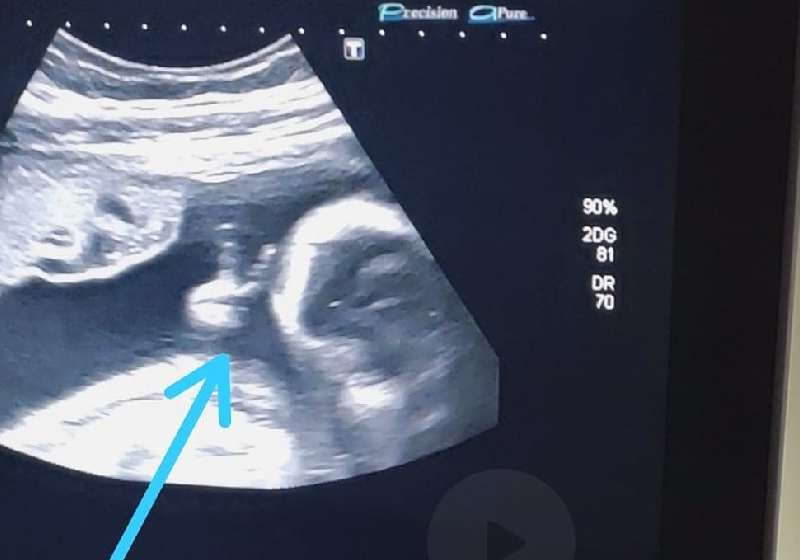

Bebê faz “V” da vitória em ultrassom e emociona pai com câncer

Um bebê apareceu no ultrassom fazendo o “V” da vitória com uma das mãozinhas e a imagem emocionou o pai, que havia pedido a Deus para não morrer porque queria conhecer o primeiro filho.

Ao acompanhar o exame de ultrassonografia de sexto mês do primeiro filho, o futuro pai viu o filho fazendo o ‘V de vitória’ com a mãozinha, dentro do útero e ficou chocado com a cena.

“Até a médica falou: ‘olha, ele fez o sinalzinho de vitória com a mão’. Eu fiquei sem acreditar”, contou.

Felipe encara a imagem como um sinal divino de que vai conseguir superar o tratamento e vencer a doença.